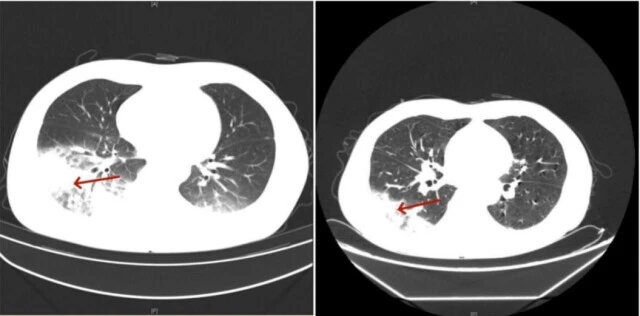

Liễu Gia, bác sĩ trực tiếp điều trị cho cô Bân, sau khi phân tích tình trạng ho ra đờm màu đỏ cam của bệnh nhân và các biểu hiện trong phổi và ngoài phổi, đã chẩn đoán cô Bân bị bệnh viêm phổi do Legionella nặng. Sau khi điều chỉnh thuốc, bệnh nhân hồi phục tốt.

Đây không phải trường hợp duy nhất, ông Nghị (55 tuổi, Trung Quốc) cũng nhập viện cùng ngày với cô Bân. Ông có tiền sử mắc bệnh tiểu đường tuýp 2, bệnh thận do tiểu đường tuýp 2 và suy thận mãn tính. Gần đây, ông được đưa đến viện với triệu chứng sốt dai dẳng, ớn lạnh và ho suốt 4 ngày. Trong quá trình kiểm tra, bác sĩ phát hiện phổi của bệnh nhân bị nhiễm trùng nặng.